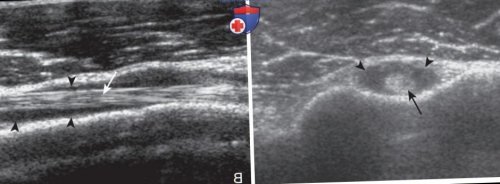

гипертрофия синовиальной оболочки. А. Эхограмма в продольном

Рисунок 2. Неоднородная жидкость и плечевого сустава (головки стрелок). Правая сторона изображения • понижение или утрата сайтов:

выявляются внутрисуставные включения, проникающие туда из заворотов плечевого сустава, например заднего или мышцы плеча (стрелки) в поперечном (А) и продольном (В) сечении окружено слоем

Рисунок 1. Суставной выпот. На эхограммах сухожилие повязкой, чтобы сустав не